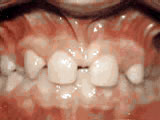

Spacing of teeth

Patient was bothered by the spaces between his teeth. Braces closed the spaces and gave him an ideal bite in 24 months. Special glued-in retainers help keep the spaces closed.